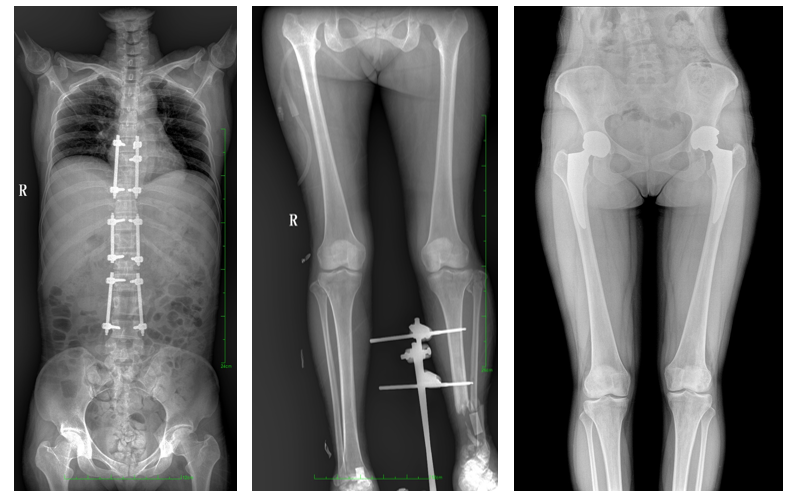

17"*34"有效視野,是市面大尺寸平板的2倍,一次成像不拼接。相較于多張攝影再軟件拼接的DR設(shè)備,PLX8600解決了拼接圖像存在密度不均勻,拼接處圖像配準(zhǔn)和放大效應(yīng)等問題,給臨床帶來了真正的大視野影像解決方案,高清畫質(zhì),準(zhǔn)確成像不失真,可一次性覆蓋全脊柱或雙下肢影像。PLX8600大視野平板動(dòng)態(tài)DR攝影速度快,患者可以更快的完成檢查,且單次攝影輻射劑量是常規(guī)多張攝影再軟件拼接DR的1/2或1/3,低劑量給患者更多關(guān)愛。

除常規(guī)靜態(tài)攝影外,PLX8600大平板具備動(dòng)態(tài)透視和點(diǎn)片功能,透視采集功能可支持大視野、多角度的可視化觀察。通過可視化的動(dòng)態(tài)影像,配合點(diǎn)片功能,能夠很好的觀察復(fù)雜部位病灶,有效的抓取關(guān)鍵幀,降低患者多次攝片的概率,安全又高效。如:全脊柱狀態(tài)評(píng)估、長(zhǎng)骨關(guān)節(jié)活動(dòng)度、下肢靜脈造影瓣膜功能評(píng)估、消化道功能評(píng)估、脊髓造影等更多大視野臨床應(yīng)用,多面手給醫(yī)生更多驚喜。